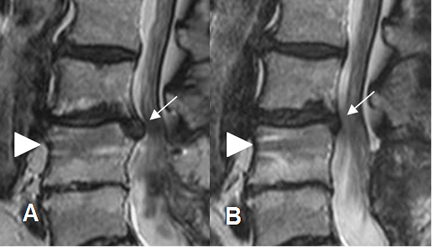

Fig 108. Regresión de hernia.

A y B: RM sagital en GE. Hernia paramediana derecha. En un control 2 años después, ha disminuido la compresión del saco dural.

Fig 110. Regresión de hernia.

A y B: RM sagital en T2. Hernia mediana en L3-L4, que después de 7 meses, muestra disminución de su tamaño y menor compresión del saco dural. Cambios degenerativos en las placas terminales de L3-L4 y

L4-L5 y artefactos sobre el cuerpo de L4, ocasionados por materia de fijación posterior. (Puntas de flecha).